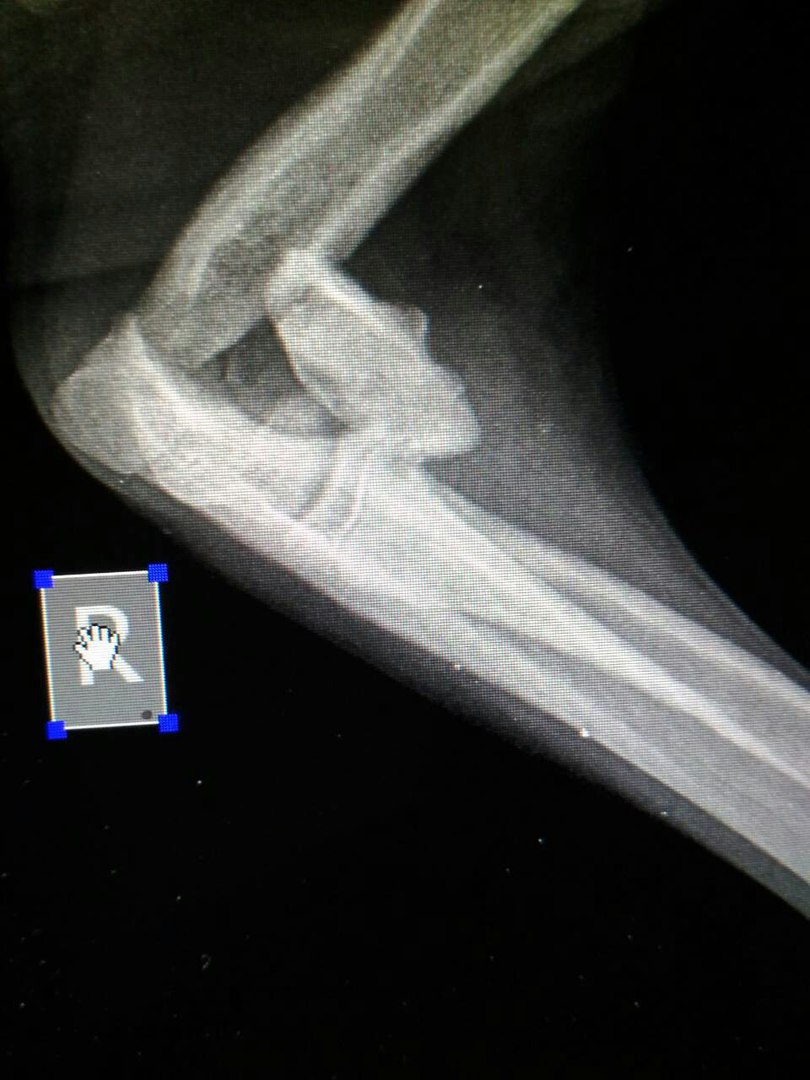

Думаю, все владельцы кошек и собак знают, что их питомцы любят поиграть. В любом зоомагазине вы найдёте специальную полочку, а то и целый стеллаж, заполненный всевозможными мячиками, игрушечными...Перелом конечности

Вопрос задан 01.12.2017 15:47 пользователем НатальяДобавить сообщение к этому вопросу или поблагодарить ветеринарного врача »

Здравствуйте!Нужна ваша помощь!Щенок попал под колёса машины...у него перелом передней лапки,лапу до локтя чувствует он ей владеет,ниже локтя она просто висит полусогнута,лапа тёплая,крообращение есть ,боли не чувствует ниже локтя.При разработке сустава собака реагирует на боль.Сустав не болтается.Есть ли надежда,что пёс сможет на неё ступать,операться хоть и хромая?Или же не делать операцию? |